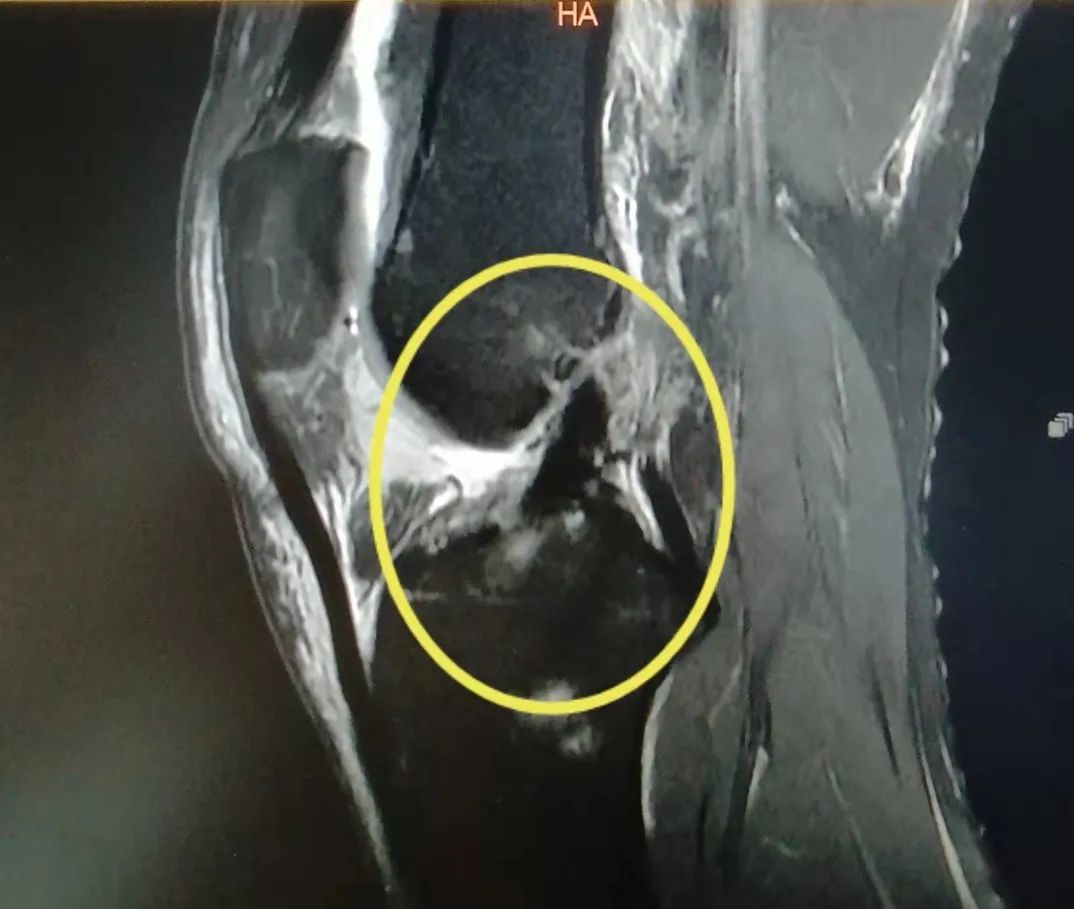

近期,同仁医院骨科程千主任团队就收治了数十例前交叉韧带断裂的病人,他们大多数是爱好运动的年轻人,不适当的运动导致了前叉韧带断裂。

前交叉韧带的主要功能是限制胫骨前移,其次是控制膝关节过伸、旋转。当运动时突然改变方向,膝关节「啪」地一声,之后就会出现肿胀,随之而来的是膝关节不稳或「打软腿」。这个时候你有可能就中招了。

几乎所有急性 ACL 损伤的患者都有关节积液,有时候还会伴有其他韧带、半月板、关节软骨、软骨下骨挫伤等。